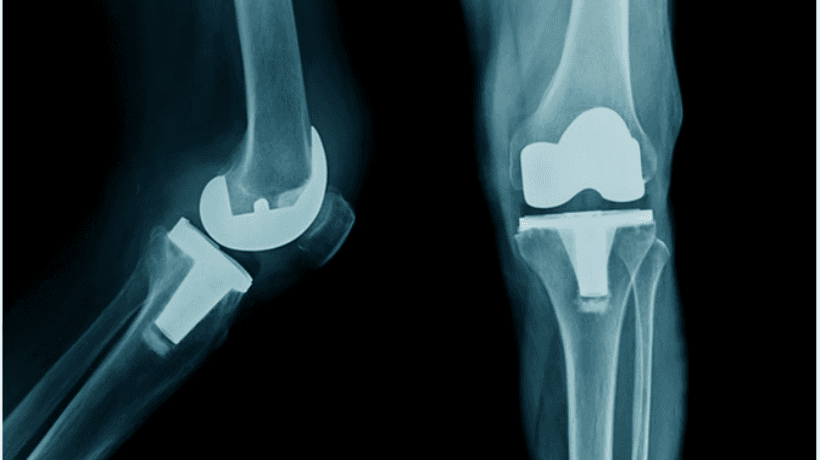

Operasi lutut biasanya mengacu padapenggantian lutut total yang dapat dilakukan dengan cara terbuka kuno atau dengan teknik modern yang kurang invasif yang dikenal sebagai artroskopi lutut.

Seorang Ahli Ortopedi menggunakan implan dan menerapkan berbagai teknik modern untuk memberikan bantuan yang diperlukan kepada pasien. Berikut ini adalah jenisnya operasi penggantian lutut dilakukan:

- Penggantian lutut total

- Penggantian lutut sebagian / uni kompartemen

- Penggantian tempurung lutut (Artroplasti Patellofemoral)

- Penggantian lutut yang rumit atau revisi

- Rekonstruksi ligamen lutut